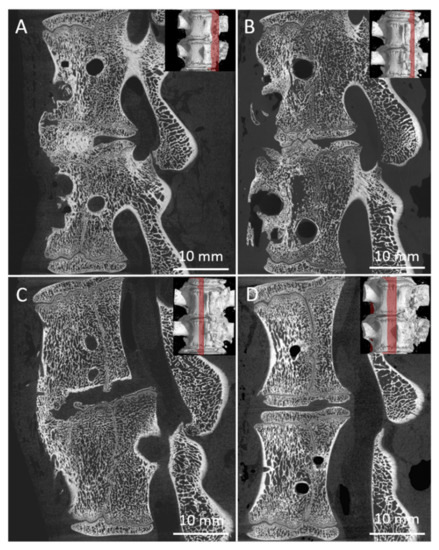

3.4. Micro-CT